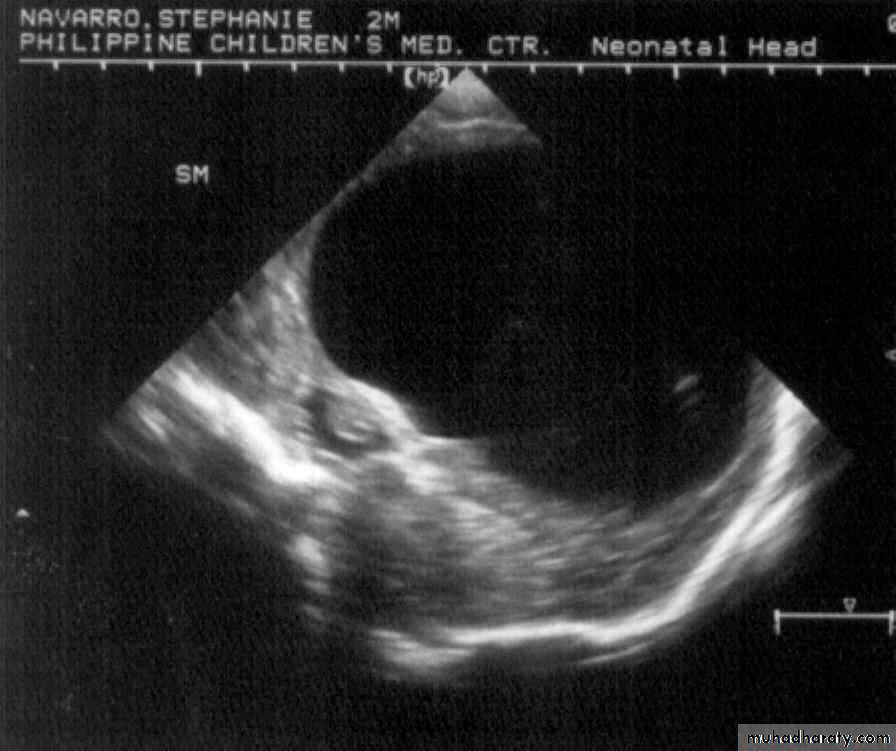

Neurulation Period11 mos old, male

Encephalocoele